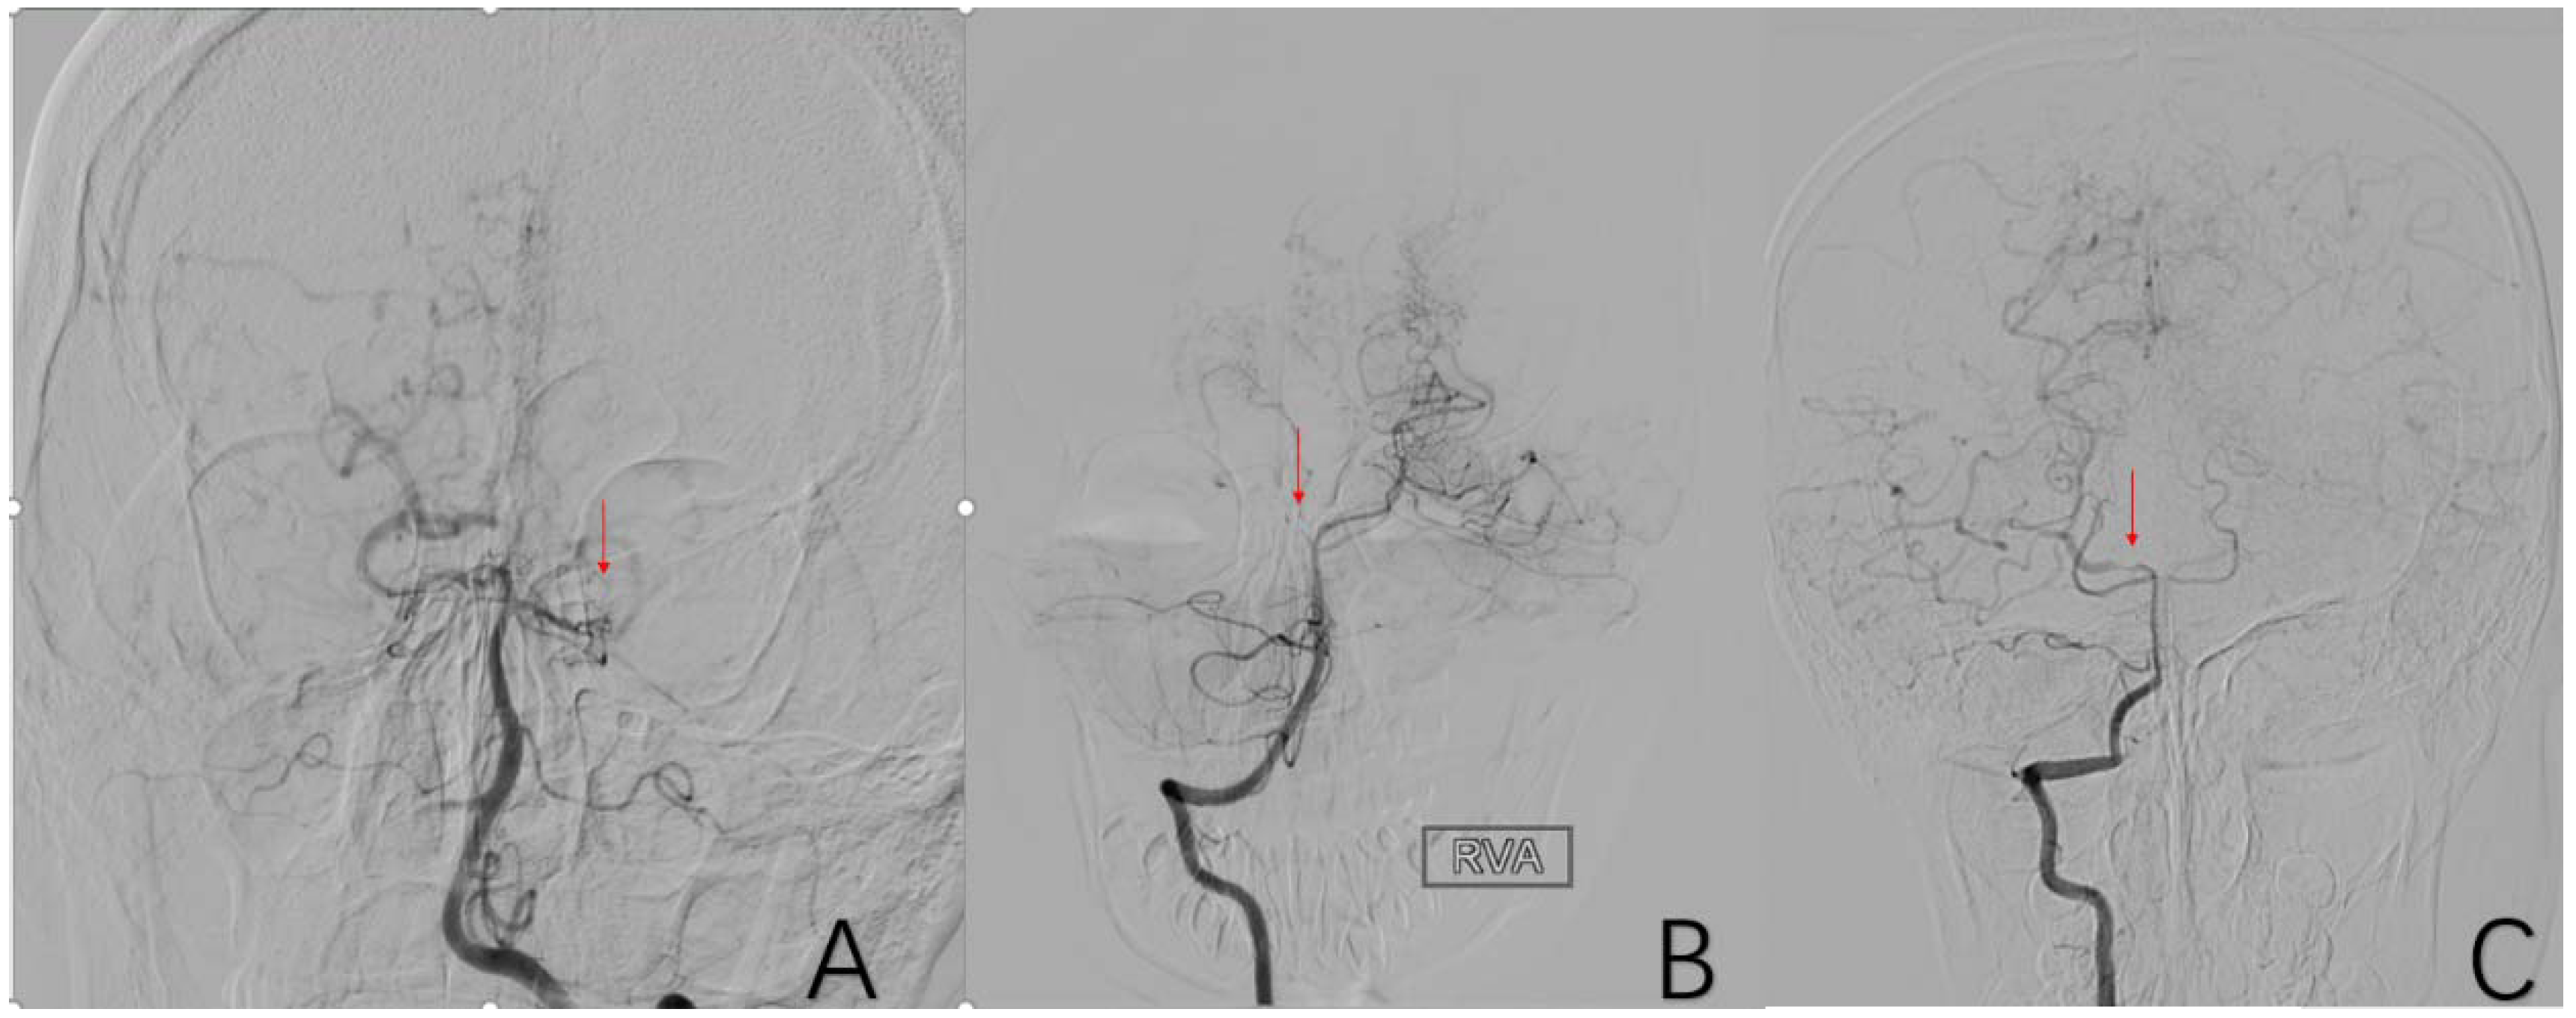

2.3.9. Factor 4 PCA Anomaly

2.3.11. Factor 6 Unstable Compensation